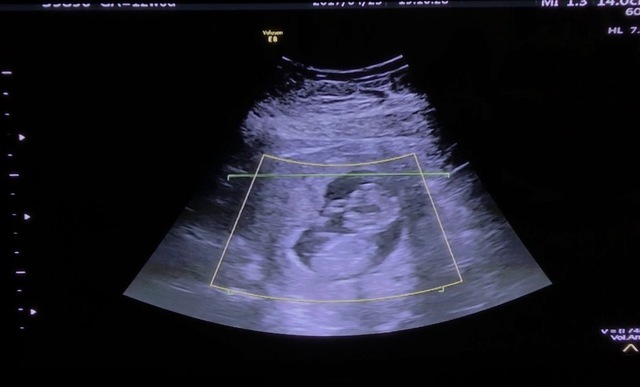

16週0日(16w0d・男の子)|うたた さん(38歳)

エコー写真撮影時のエピソード:

安定期に入って初めての4Dエコー。カラーの立体で見えて、今までエイリアンで見えていた我が子がとてもとてもかわいく感じました。

恥ずかしがってか?顔は見せてくれませんでしたが、全身が写った貴重な1枚です。